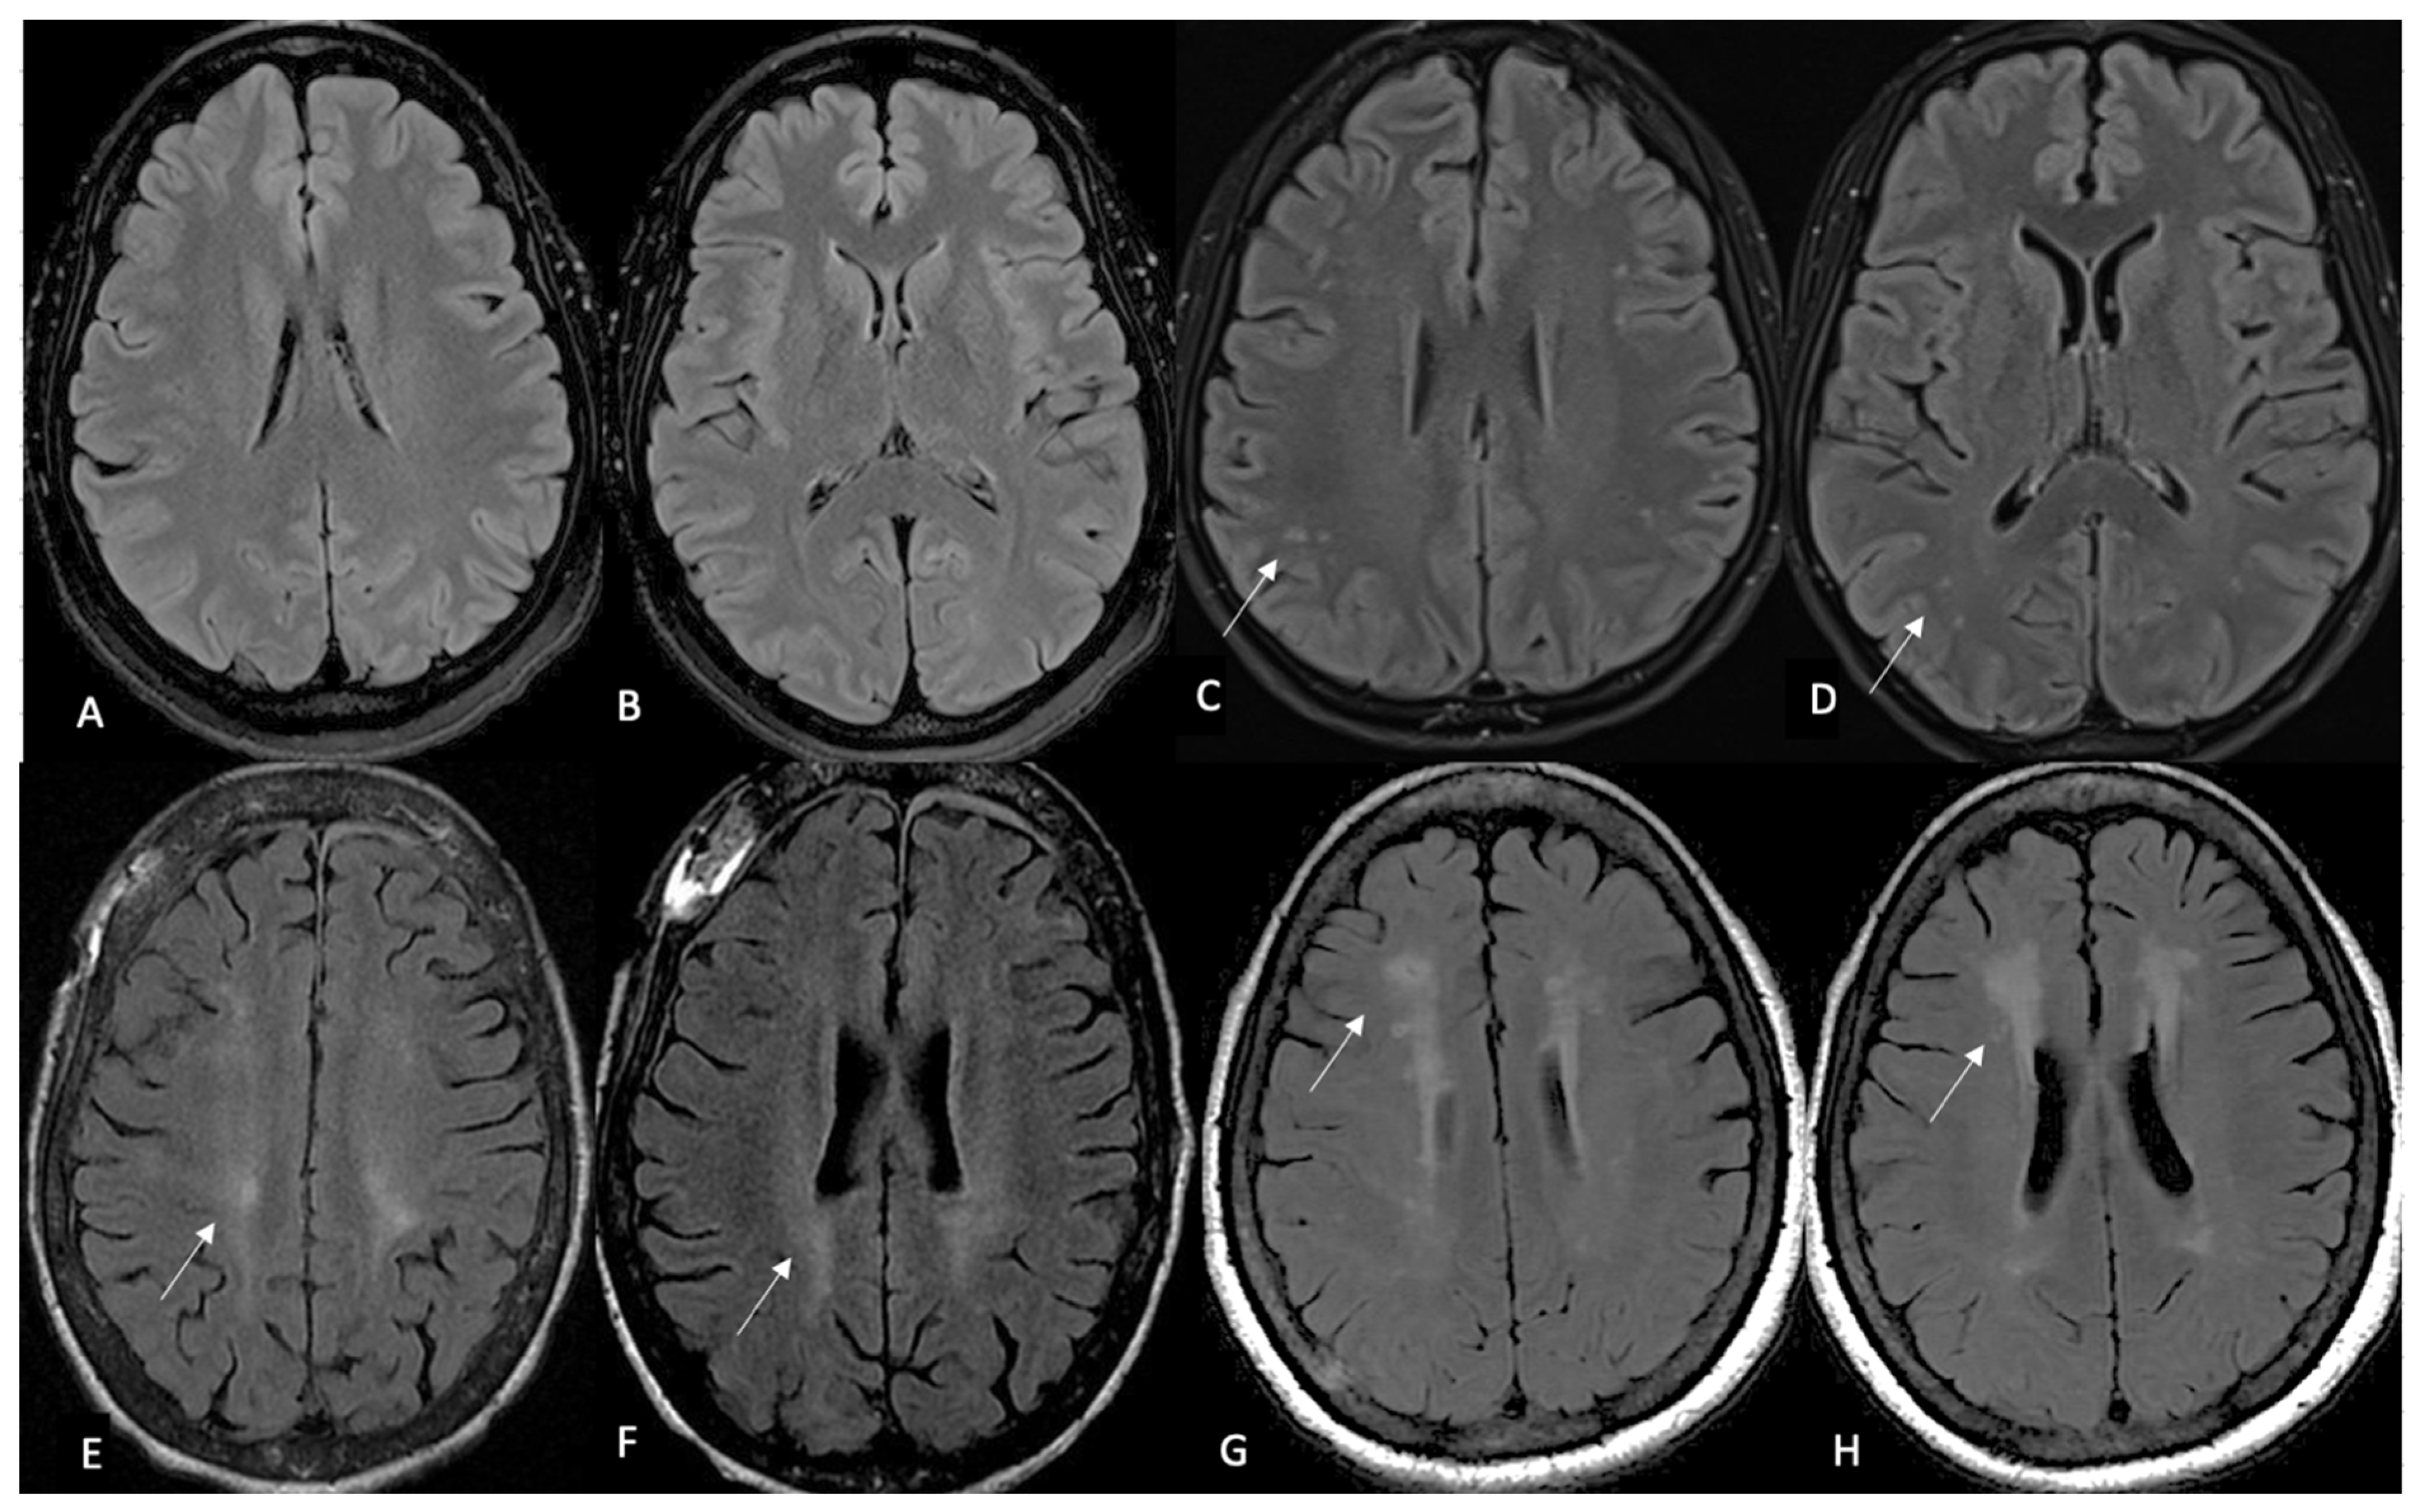

| White Matter Lesions | Rating Scale for MRI |

|---|---|

| 0 | No lesions |

| 1 | Focal lesions |

| 2 | Beginning confluence |

| 3 | Diffuse involvement of entire region, with or without involvement of U fibers |